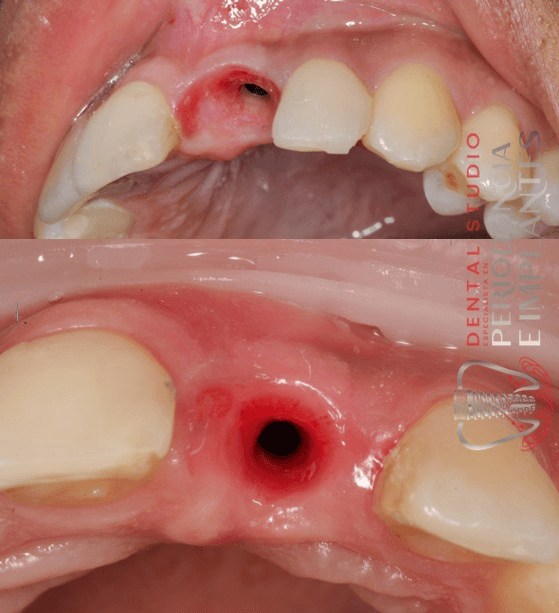

Manejo de tejido blando post implante dental

Manejo del perfil de emergencia con injerto de tejido blando de zona retromolar. El perfil de emergencia en implantes dentales es crucial para el éxito estético y biológico, ya que moldea la encía para lograr una apariencia natural del diente